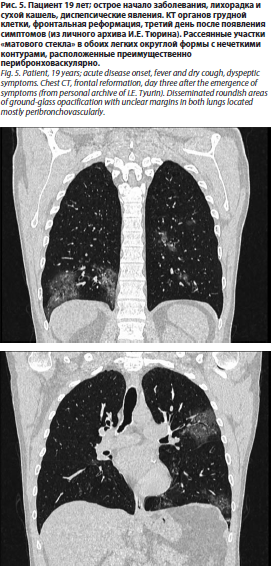

Что же касается результатов КТ, то они, также не являясь строго специфичными, могут оказать дополнительную помощь при обнаружении таких рентгенологических находок, как участки «матового стекла», утолщение стенок бронхов/бронхиол, цетрилобулярные очаги (рис. 4, 5).